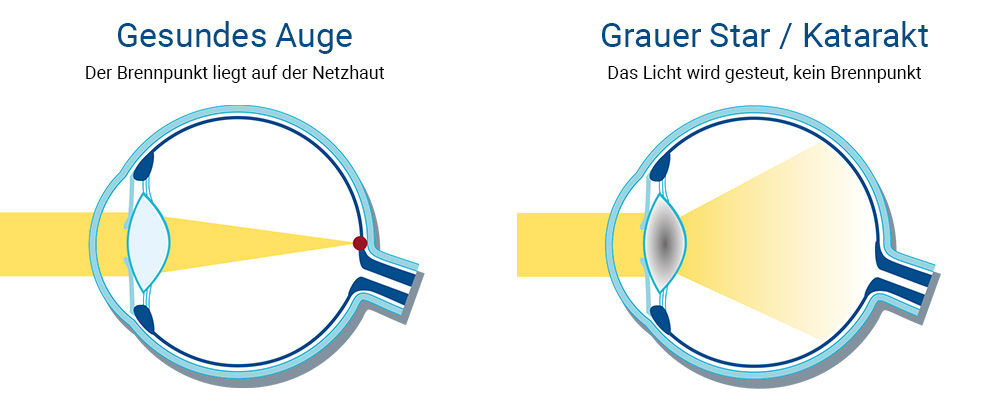

module_contentBei jedem Menschen entwickelt sich früher oder später ein Grauer Star, die Trübung der natürlichen Linse im Auge, welche eine Kataraktextraktion und die Implantation einer klaren künstlichen Intraokularlinse notwendig macht. Die Katarakt-Operation ist die am häufigsten durchgeführte Operation in der gesamten Medizin. In vielen Ländern ist die Kataraktchirurgie, gemessen an der Gesamtzahl der Eingriffe, die am häufigsten durchgeführte Operation.

Der Graue Star – auch Katarakt genannt – ist eine meist im mittleren Alter, etwa ab dem 50. Lebensjahr, einsetzende Augenerkrankung, die unbehandelt die häufigste Ursache für Erblindung darstellt. Bei Menschen mit einem fortgeschrittenen Grauen Star ist eine graue Färbung hinter der Pupille zu erkennen.

module_contentJe nach Intensität und Position des Katarakts im Auge sind die Symptome bei den Betroffenen unterschiedlich ausgeprägt. Grauer Star betrifft in der Regel beide Augen, kann aber auch nur eines betreffen, was als höheres Risiko für Langzeitschäden gilt.